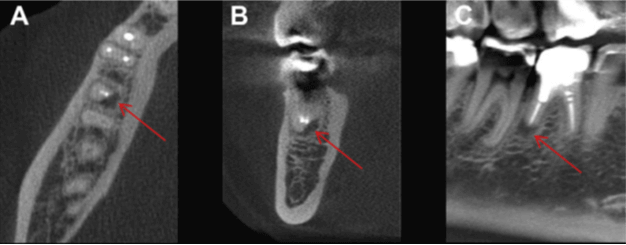

Sin embargo, la reabsorción radicular inflamatorio es una lesión asintomática, lo cual hace más complejo su diagnóstico y tratamiento. El criterio estándar para el diagnóstico de este tipo de reabsorción se da por medio del análisis microscópico. Las imágenes radiográficas convencionales se han utilizado con frecuencia para la detección y seguimiento de la reabsorción radicular inflamatoria. Sin embargo, el acortamiento apical, los defectos dentarios radiculares laterales o cervicales, el agrandamiento del conducto radicular y los defectos radiolúcidos radiculares externos no es posible identificarlos en una evaluación radiográfica en su fase inicial cuando el proceso de reabsorción inflamatoria es discreto, o debido a las limitaciones de las radiografías convencionales conocidas como la distorsión geométrica o la superposición.

La tomografía computariza cone beam ofrece múltiples ventajas que pueden influir de forma considerable en las decisiones tomadas por los odontólogos para la elaboración de un plan de tratamiento. La detección precoz de la reabsorción radicular inflamatoria puede conducir a una intervención oportuna y a mejores resultados del tratamiento. Por medio de la tomografía computarizada cone beam se puede evaluar la extensión real de la reabsorción radicular inflamatoria analizando todas las dimensiones de la lesión mediante la evaluación de los cortes axiales, coronales y sagitales. Además, se pueden realizar mediciones del tamaño de los defectos radiculares como parte de un seguimiento longitudinal, lo cual es útil para determinar si la lesión si el proceso de reabsorción radicular inflamatoria se encuentra en una fase de detención, en fase de reparación o en franca progresión. El análisis tomográfico puede modificar las diferentes hipótesis diagnósticas, asi como los planes de tratamiento que podrían afectar el pronóstico del mismo en diferentes escenarios clínicos. El pronóstico de esta lesión se ve afectado por la vitalidad de la pulpa, así como por la localización de defecto, extensión y el número de superficies afectadas. Además, la tomografía computarizada cone beam tiene muchas ventajas sobre otros métodos cuando se utiliza en situaciones clínicas en las que el seguimiento clínico es esencial, como la reparación de dientes permanentes luxados, reabsorción cervical progresiva, reabsorción dentaria causada por dientes impactados o reabsorción severa de incisivos a causa del tratamiento de ortodoncia.